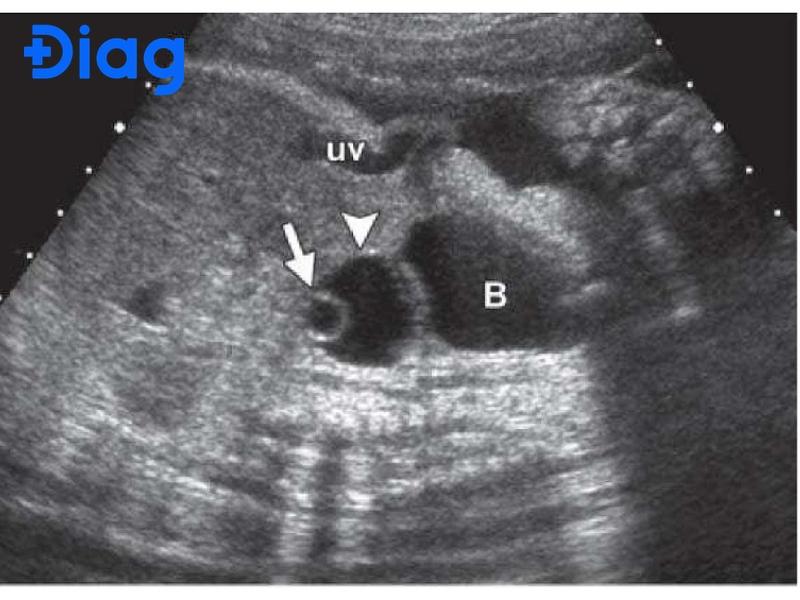

Nang echo trống buồng trứng (nang không hồi âm) là thuật ngữ y khoa mô tả một khối chứa dịch bên trong buồng trứng. Trên kết quả siêu âm, nang hiển thị là vùng trống, tức không phản hồi tín hiệu siêu âm (echo), nên gọi là echo trống. Đây là tình trạng phổ biến ở phụ nữ độ tuổi sinh sản.

Nang echo thường là dấu hiệu của u nang buồng trứng có chứa dịch lỏng bên trong (u nang nước) hoặc nang cơ năng. Nang echo trống thường có kích thước từ vài mm đến vài cm, có thể xuất hiện ở buồng trứng trái hoặc phải. Ví dụ, nang echo trống buồng trứng trái hay nang echo trống buồng trứng phải đều là những thuật ngữ chỉ vị trí của nang trên buồng trứng tương ứng.